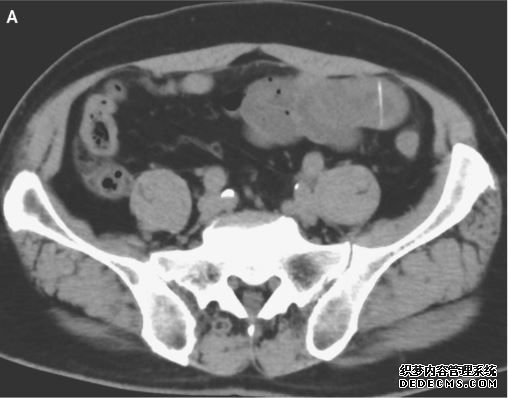

对该名男子腹部的CT扫描显示,他的小肠被“一个线性高密度的身体”刺穿。换句话说,一个看起来很像小骨头的东西卡在了他的肠子里。